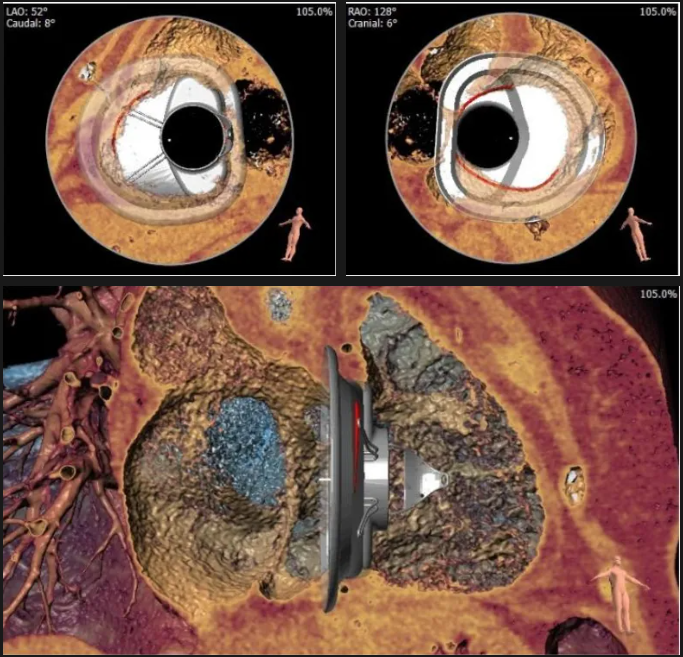

術(shù)前心臟CT評估

三尖瓣環(huán)平均周長徑54.3mm,最大直徑57mm

心房側(cè)周長平均徑(封堵高度)74.0mm

三尖瓣環(huán)切線位夾角 103°

術(shù)中經(jīng)食道超聲輔助下可見LuX-Valve Plus夾持件抓捕瓣葉狀態(tài)良好,夾持件在位,室間隔錨定位置良好,假體瓣膜整體錨定狀態(tài)穩(wěn)固。

術(shù)后三維超聲

術(shù)后即刻經(jīng)食道超聲可見,三尖瓣假體瓣膜位置合適,牛心包瓣葉運(yùn)動狀態(tài)良好,開閉正常,瓣周及瓣葉對合緣處未見明顯返流,心電圖及心包狀態(tài)較術(shù)前無明顯變化。